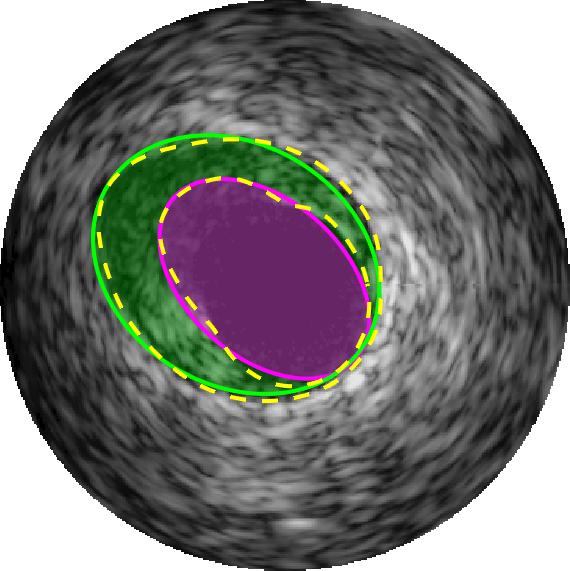

Qualitative evaluations are illustrated in Figure 4 and show the successful segmentation results of the proposed EREL selection strategy for 20 IVUS frames. The lumen areas are highlighted by the magenta colour while the media regions are green. Also, the manually annotated contours for both lumen and media are drawn as yellow dashed lines. As we can see, the chosen frames contain a variety of lumen and media morphologies.